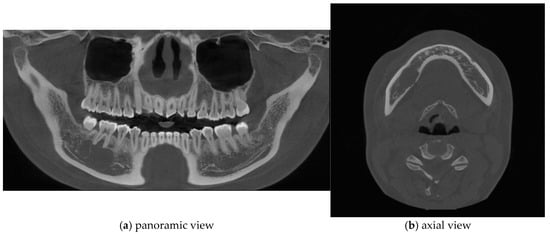

A 25-year-old female was referred to the Department of Oral and Maxillofacial Surgery from a local dental clinic with a primary concern of an intraosseous lesion located below the root apex of the right mandibular first molar. The patient did not report any clinical symptoms. Panorama revealed a multilocular radiolucent lesion with relatively well-defined borders and sclerotic margins in the region of the right mandibular molar. In addition, root resorption was observed in the right mandibular second premolar and first molar (Figure 1). Cone-beam computed tomography (CBCT) revealed thinning of the lingual cortical bone in the areas surrounding the right mandibular second premolar and first molar, as well as inferior displacement of the right mandibular canal (Figure 2). Both the right mandibular second premolar and first molar exhibited slight mobility and percussion sensitivity, while electric pulp testing was positive. Incisional biopsy was the ameloblastoma. To treat the lesion and minimize the risk of recurrence, resection and reconstruction were planned, and virtual surgical planning was performed in collaboration with the SEEANN solution (SEEANN solution, Seoul, Korea). To ensure accurate translation of the VSP to the actual surgery, template models were fabricated for preoperative simulation and intraoperative reference, and surgical guides were designed with multiple registration points for optimal positioning verification during the procedure.

Figure 1.

A multilocular radiolucent lesion with relatively well-defined borders and sclerotic margins in the right mandibular molar region, along with root resorption of the right mandibular second premolar and first molar (red arrow).

Figure 2.

Cone-beam computed tomography (CBCT) imaging revealed thinning of the lingual cortical bone in the region of the right mandibular second premolar and first molar, as well as inferior displacement of the right mandibular canal.